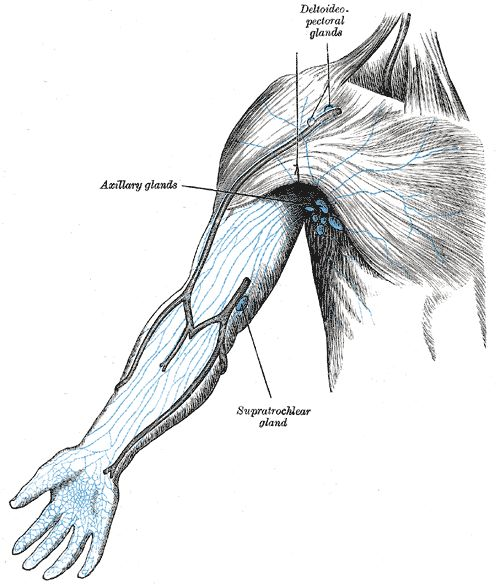

这是因为这些潜伏在人体的VZV病毒,正伺机而动,随时准备肆虐一番。只要人体的免疫大军疏于防范,它们就会悄悄溜进部分淋巴结里进行繁衍增值。紧接着,它们又会大摇大摆地随着血液和淋巴系统等,逐渐扩散到全身。没过多久,患者就会陆续出现发烧、肌肉酸痛,食欲不振,四肢乏力等常见的病毒感染症状。

淋巴遍布全身,并通过淋巴管循环,图为手臂上的淋巴管

原来在治疗水痘的过程中,人体免疫系统确实把体内大多数的VZV病毒消灭掉。但仍会残留一些不能被血清中的抗体完全中和的VZV病毒。这些病毒发挥着自己天然亲近神经的特性,顺着皮肤的上皮感觉神经末梢不断逃离免疫大军攻击。最后,它们躲进了脊髓后根神经节的神经元或是颅神经的感觉神经节里,并在长期定居了下来。